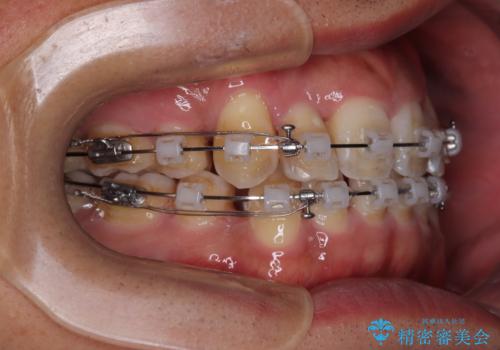

そこで、上下左右の第一小臼歯を抜歯し、歯が並ぶためのスペースを確保し叢生を解消する治療計画を立てました。

矯正装置は、審美性と費用面のバランスを考慮して、プラスチックブラケットとメタルワイヤーを使用しました。

透明感のあるブラケットを用いたため、従来の金属装置よりも目立ちにくく、日常生活での見た目の不安も軽減できます。